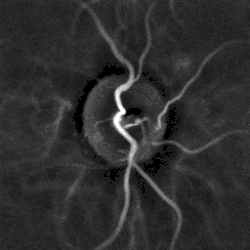

| Hypertensive retinopathy with AV nicking and mild vascular tortuosity | |

- Arteriolar changes, such as generalized arteriolar narrowing, focal arteriolar narrowing, arteriovenous nicking, changes in the arteriolar wall (arteriosclerosis) and abnormalities at points where arterioles and venules cross. Manifestations of these changes include Copper wire arterioles where the central light reflex occupies most of the width of the arteriole and Silver wire arterioles where the central light reflex occupies all of the width of the arteriole, and "arterio-venular (AV) nicking" or "AV nipping", due to venous constriction and banking.